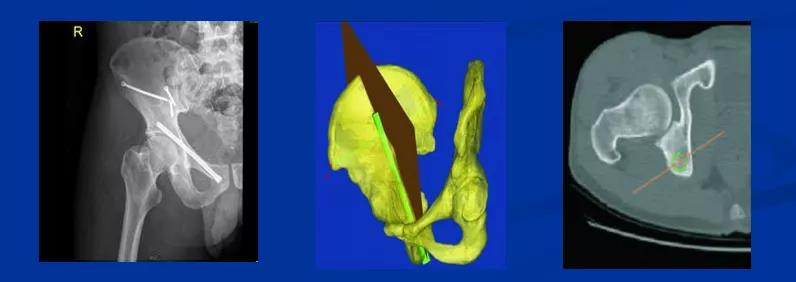

——典型案例——

微创插板病历后路有限切开,结合前路微创插板内